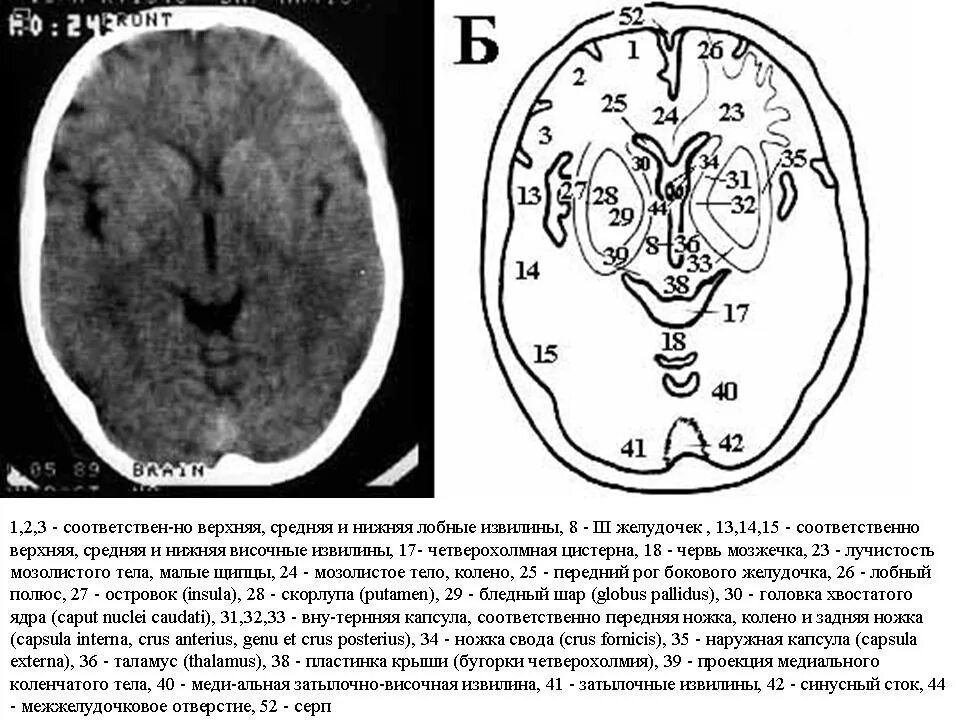

Цистерны на кт